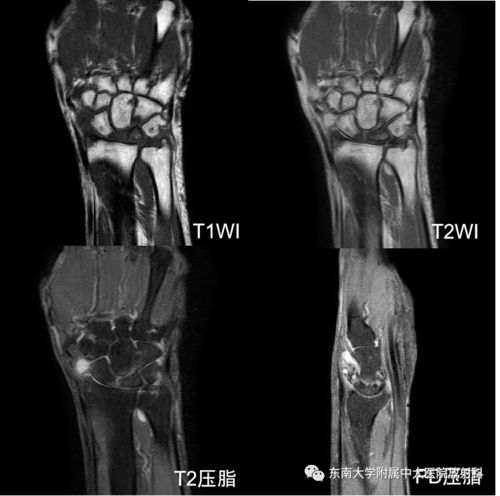

骨折是骨骼系统最常见的疾病之一,通常由外伤引起。根据骨折的严重程度,可以分为完全骨折和不完全骨折。完全骨折是指骨骼完全断裂,不完全骨折则是指骨骼部分断裂。骨折的常见症状包括疼痛、肿胀、畸形和功能障碍。治疗骨折通常需要固定、手术和康复训练。

骨关节炎是一种慢性关节疾病,主要表现为关节软骨的退行性变和关节边缘骨赘的形成。这种疾病常见于中老年人,尤其是负重关节,如膝关节、髋关节等。骨关节炎的症状包括关节疼痛、僵硬、肿胀和活动受限。治疗骨关节炎的方法包括药物治疗、物理治疗和手术治疗。